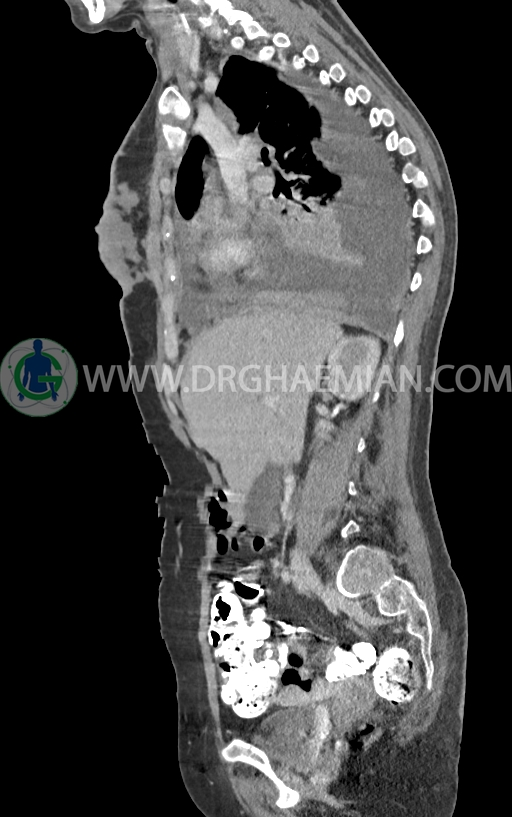

در سی تی اسکن اسپیرال ریه و مدیاستن -شکم و لگن با کنتراست خوراکی و وریدی (مولتی دیدکتور 16 با مقاطع ظریف و بازسازی های ساژیتال و کرونال) :

–توده نسج نرمی بسیار بزرگ به حداکثر دیامتر 82mm همراه با مارژین لبوله در پستان راست دیده شد که همراه با گسترش و درگیری پوست و نیپل بوده و مطرح کننده ضایعه تومورال و بدخیم می باشد.

–این توده در قسمت هایی عضله پکتورالیس این سمت را abut کرده است.

– ندول های نسج نرمی اقماری متعدد در مجاورت فوقانی این توده با حداکثر دیامتر کمتر از 17mm

– تعدادی لنف نود هتروژن و irregular با حداکثر SAD<12 در آگزیلاری راست

–ضایعات استخوانی لیتیک فراوان منتشر در تمامی طول ستون مهره و لگن رویت شدند که مطرح کننده متاستاز استخوانی می باشند.

–شکستگی پاتولوژیک در مهره های T6 , T10 , T11

–کیفوز موضعی در Level T10 , T11 در ستون مهره

–رتروپالشن شکستگی مهره T10 همراه با ایجاد تنگی کانال نخاعی